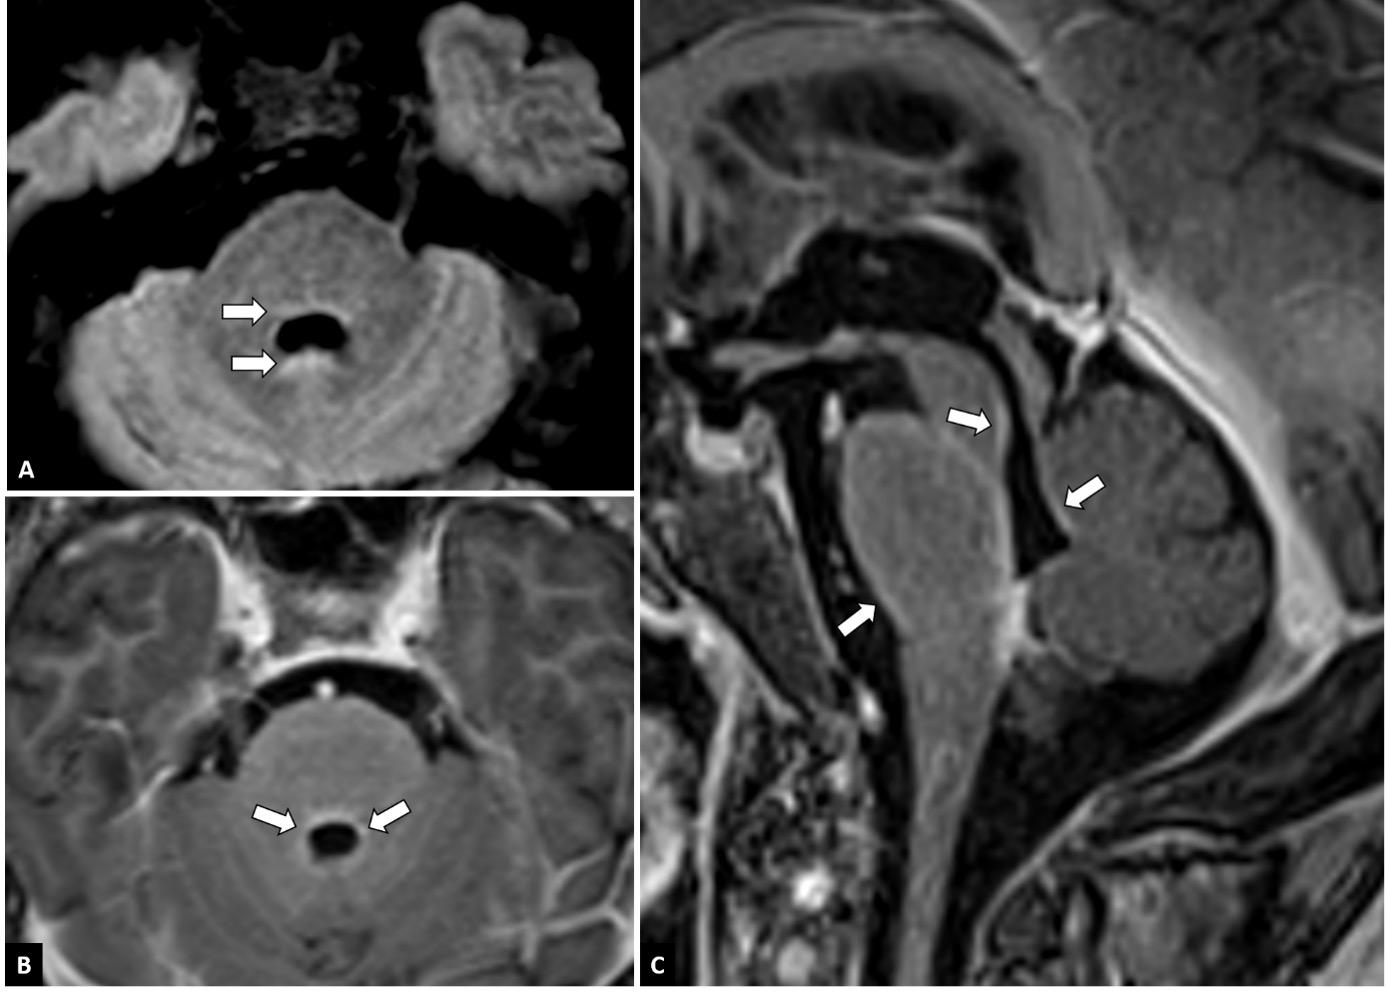

On lumbar puncture, there was an elevated opening pressure (37 cmH20 and 45 cmH20 with Valsalva). Cerebrospinal fluid (CSF) analysis demonstrated a raised white blood cell count (5/µL) and elevated protein (100 mg/dL) during treatment with amoxicillin-clavulanate. The latter was administrated because of a urinary infection with culture positive for ciprofloxacine-resistent E. coli. Antibiotic treatment was later on switched to ceftriaxone and co-trimoxazole when the culture was known. CSF gram stain was negative. The CSF cultures for bacteria and mycobacteria did not show any organisms. Polymerase Chain Reaction (PCR) for Herpes Simplex Virus, Epstein-Barr Virus, Cytomegalovirus, Toxoplasma gondii and Hepatitis B and C were negative. CSF cytology and flow cytometry were unremarkable (13). Anatomopathological examination of CSF did not show malignant cells. Panels for paraneoplastic antibodies; antinuclear antibodies (ANA), antiribonucleoprotein autoantibodies (Anti-RNP), anti-small nuclear ribonucleoprotein antibodies (snRNP), antibodies to SSa antigen (Anti-Ro-52 and anti-Ro-60), antibodies to SSb antigen (Anti-La), Anti-Scl-70, Anti-Jo-1, Anti-CENP-B, Anti-DFS70 and antineutrophil cytoplasmic antibodies (ANCA) and autoimmune encephalitis antibodies; anti-NMDA receptor antibodies (anti-NMDAR); anti-smooth muscle antibodies (Anti-SMA), anti-mitochondrial antibodies (Anti-AMA), anti-liver-kidney microsomal antibodies (Anti-LKM) and anti-tissue transglutaminase IgA (Anti-tTg-IgA) remained negative on serum and on CSF. Meanwhile PET-CT showed diffuse lung abnormalities and enlarged mediastinal and hilar lymph nodes consistent with pulmonary sarcoidosis; no tumoral masses were detected. Electroencephalography (EEG) showed no signs of epileptic activity and a normal alpha rhythm although many artefacts were present. Contrast-enhanced magnetic resonance imaging (MRI) demonstrated infratentorial leptomeningeal enhancement, most notably around the brain stem and in the fourth ventricle walls (Figure 1). Angiotensin-converting enzyme (ACE) was normal in serum and CSF (23 U/L and 9 U/L).

Figure 1

MRI features. Axial FLAIR-weighted images at the level of the fourth ventricle (A) show discrete FLAIR-hyperintense signals around the fourth ventricle (arrows). On axial (B) and sagittal (C) post-contrast T1-weighted images of the fossa posterior, leptomeningeal contrast enhancement can be seen around the brainstem and in the walls of the fourth ventricle (arrows).

Taking into account the patient’s history of pulmonary sarcoidosis with pathologic confirmation of systemic granulomatous disease 7 years prior, the clinical presentation and MRI features typical of granulomatous inflammation and the rigorous exclusion of other causes, a diagnosis of probable neurosarcoidosis was made following the 2018 Neurosarcoidosis Consortium Consensus criteria (15). This patient developed catatonia and delirium with persistent psychotic symptoms in the context of a urinary tract infection, bilateral pneumonia due to sarcoidosis and a probable diagnosis of neurosarcoidosis Figure 1.